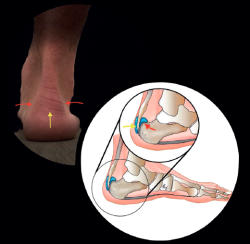

Figure 2. Topographic correlation. Distal central pain: tendinopathy, preachilleal bursitis, enthesophytes (yellow arrows). Lateral and medial pain: retrocalcaneal bursitis, conflict with the posterior calcaneal tuberosity (red arrows). Illustration authorship: Dr. Álvaro Fernández.

Knowing the structures involved, the topographic anatomy is very useful in this location (Figure 2).